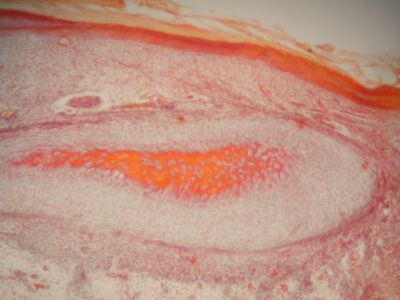

Fetal finger - histology slide

This is a histology slide of a human fetal finger.

Histology slide courtesy of Florida State University.